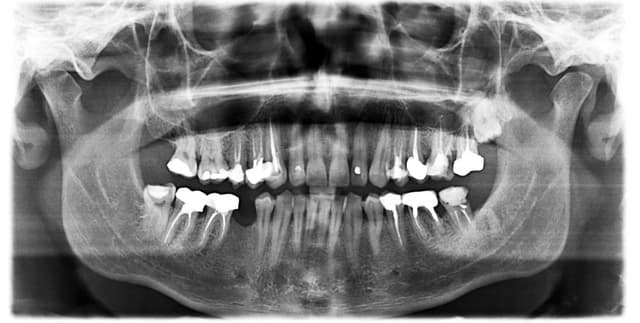

This dataset is designed for the analysis and diagnosis of dental radiography. It serves to help dentists identify changes in hard and soft tissues, evaluate facial and mouth injuries, and monitor teeth and jawbone development in children. The dataset is provided as a zip file containing three folders: Train, Test, and Valid, making it suitable for developing image classification models using techniques such as Convolutional Neural Networks (CNN), YOLO, or SSD.

The dataset includes metadata for each image, detailing detected prosthetics and issues. Based on the provided sample, the relevant columns are:

- class: The category of the dental finding or prosthetic identified, such as 'Implant' or 'Fillings'.